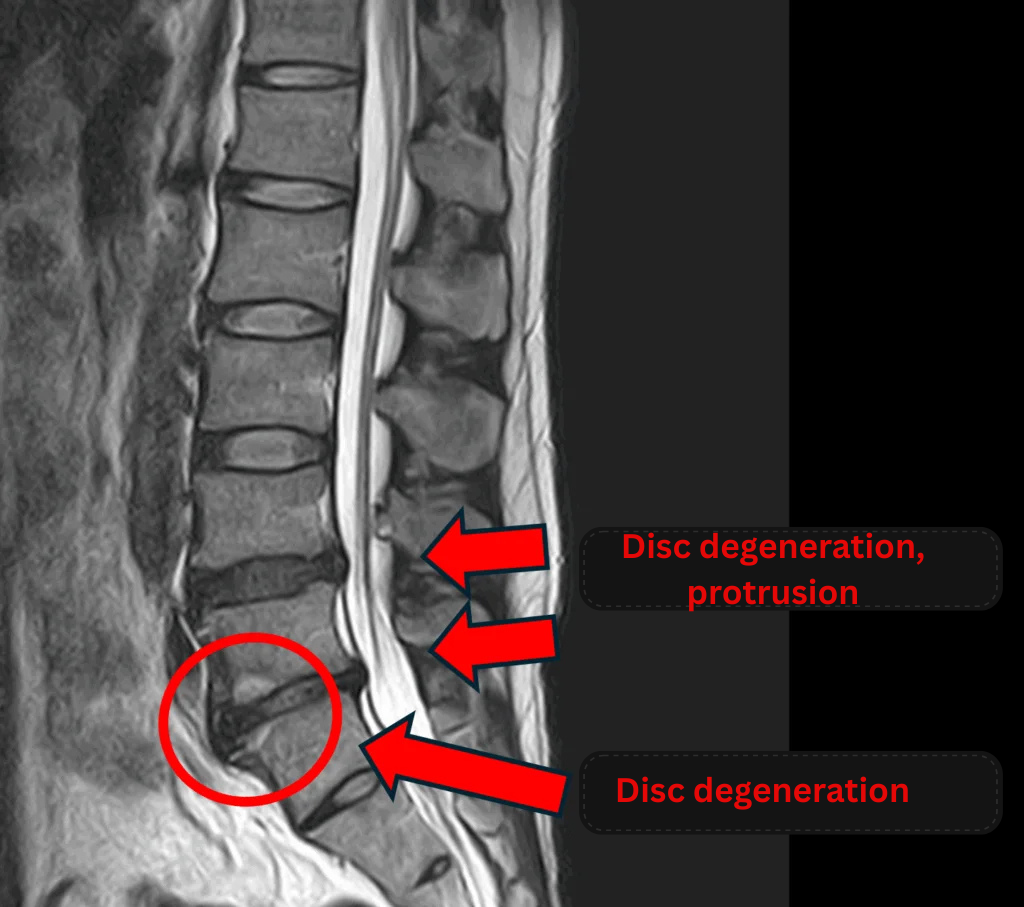

Imaging and findings

- L4/5: Disc degeneration, disc bulging

- L5/S: Disc degeneration, disc bulging, endplate degeneration

The above findings were also observed on the imaging.

These findings suggest that compression in the spinal canal due to disc changes at L4/5 and L5/S is the most likely cause of symptoms.